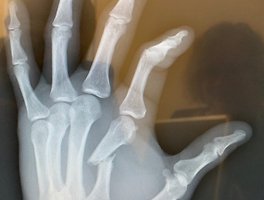

| [동영상] UFC 구스타프손 은퇴시킨 앤서니 스미스, 왼손 골절 X레이 사진 공개… “무슨 일 있어도 싸움 끝낸다” (0) | 2019.06.06 |